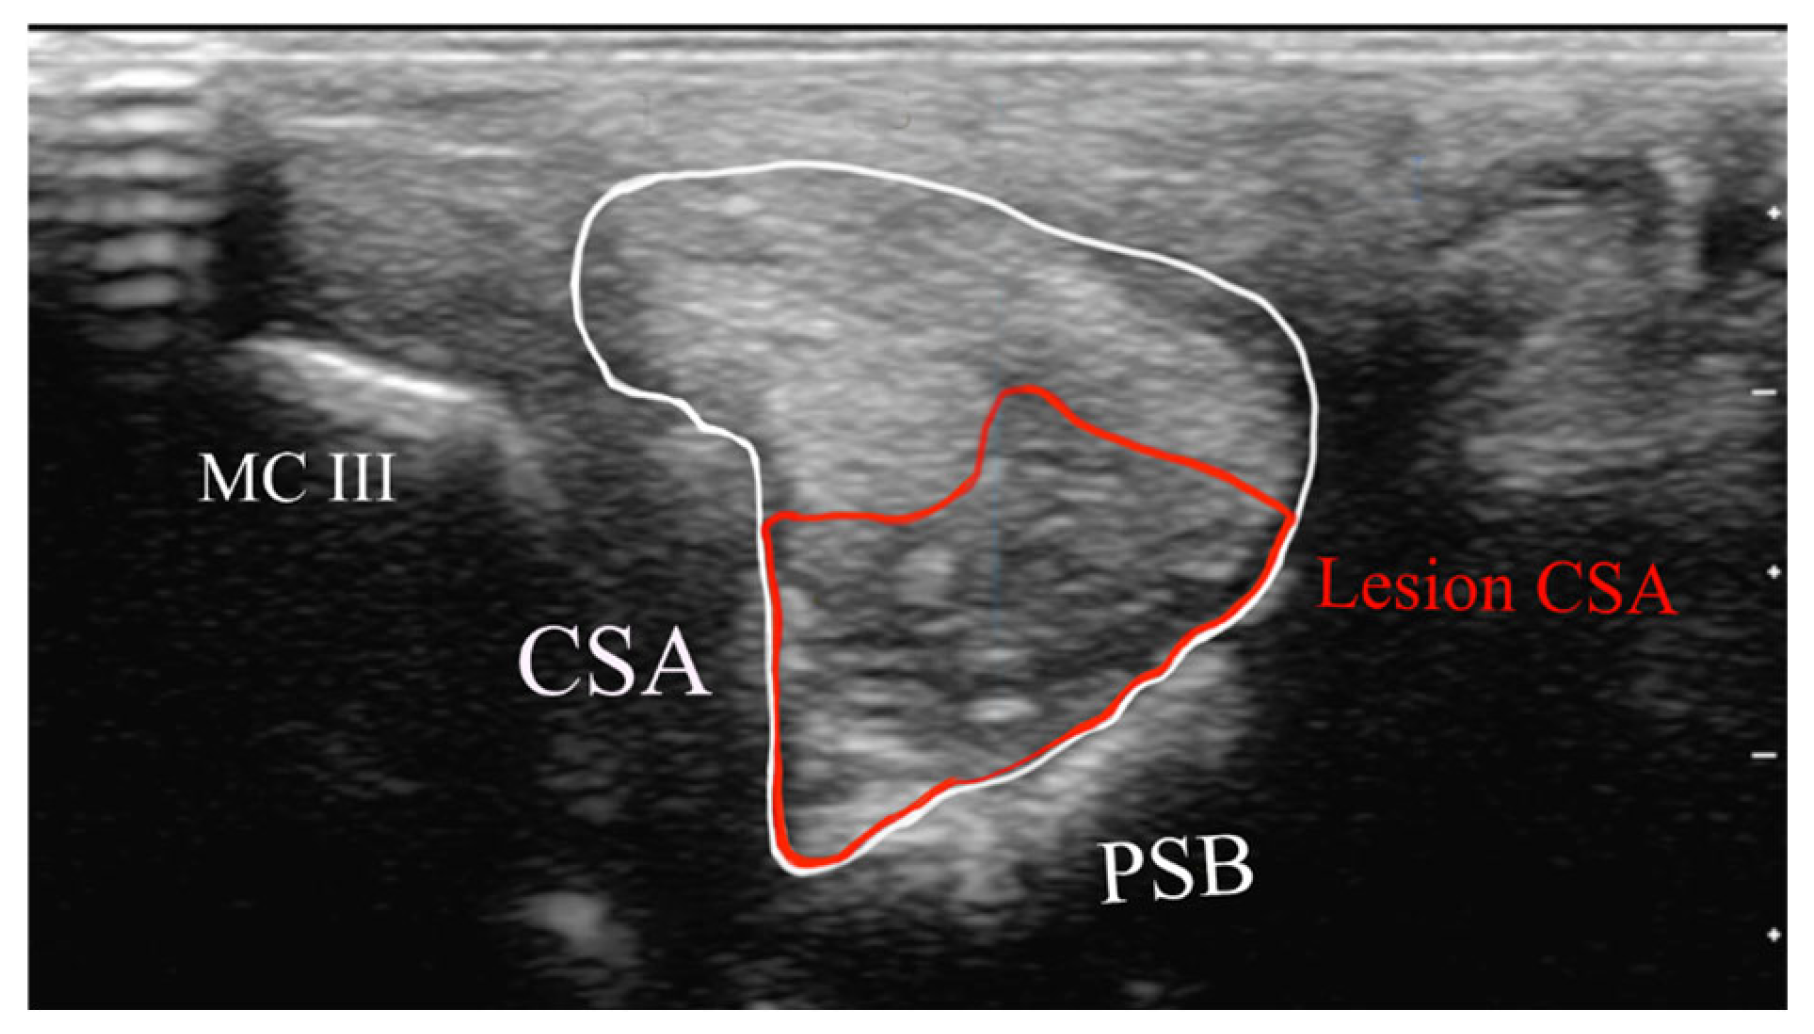

- Cross-sectional area of the SL branch (cm2);

- Lesion CSA (cm2).

2.4.1. Classification of Ultrasonographic Lesions